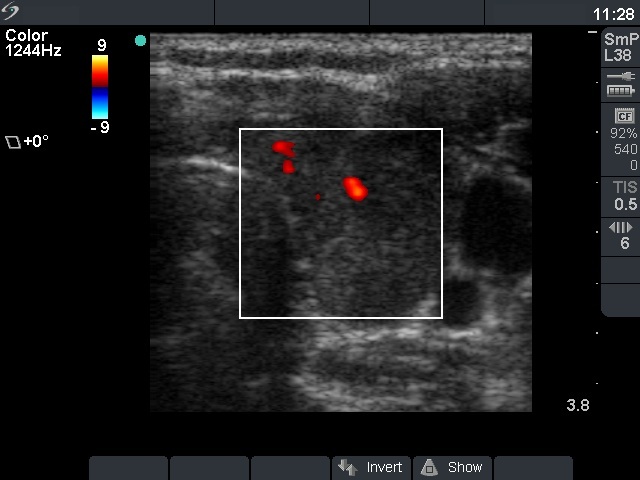

Follow-up examination 4 months after initial investigation (third row of images):

Clinical presentation: The inflammatory complaints of the patient suddenly stopped within 24 hours of the steroid intake and did not recur after discontinuation of the steroid.

Palpation: no abnormality.

Functional state: subclinical hypothyroidism with TSH-level 4.92 mIU/L, FT4 13.7 pM/L. Erythrocyte sedimentation rate was 11 mm/H, CRP was 0,9 mg/L.

Ultrasonography. The thyroid became smaller and the echo structure had normalized. Nevertheless, there were several minimally-moderately hypoechogenic areas in both lobes. There were no significant changes in the vascularization.